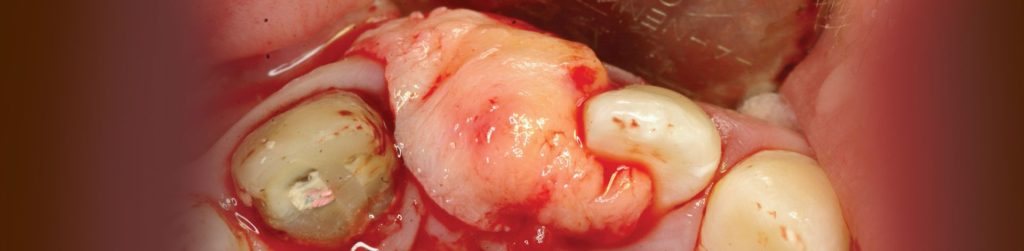

בסמוך למרפאתנו הקמנו חדר הרצאות חדשני וייחודי. ייעודו של האגף החדש הינו להגשים חלום יקר לליבנו, לממש ולקיים מרכז להכשרה קלינית לרופאים ובהדרכה אישית: A PRIVATE ACADEMY. במרכז יתקיימו הרצאות, קורסים עיוניים ומעשיים בהם תהיה צפייה בניתוחים בשידור חי, מחדר הניתוח בזכות מיטב הטכנולוגיה החדשנית. במתחם החדש, אנו נארגן מגוון רב של פעילויות, ומאמינים כי ביכולתנו לתרום מניסיוננו לטובת ציבור רופאי השיניים הכלליים. הקורסים מיועדים לכלל ציבור רופאי השיניים המעוניינים להעשיר את בסיס הידע ואת יכולתם הקלינית בתחומים שונים (פריודונטיה, אימפלנטולוגיה ואסתטיקה), דבר שישרת אותם במרפאתם. המרצים יהיו רופאי המרפאה יחד עם רופאים בכירים ומומחים נוספים אשר יצטרפו לצוות.